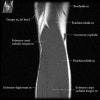

- Sagittal section

1) Biceps Brachii tendon and Brachiallis muscles

2) Radial head for radiographically occult fractures

3) Distal Triceps tendon